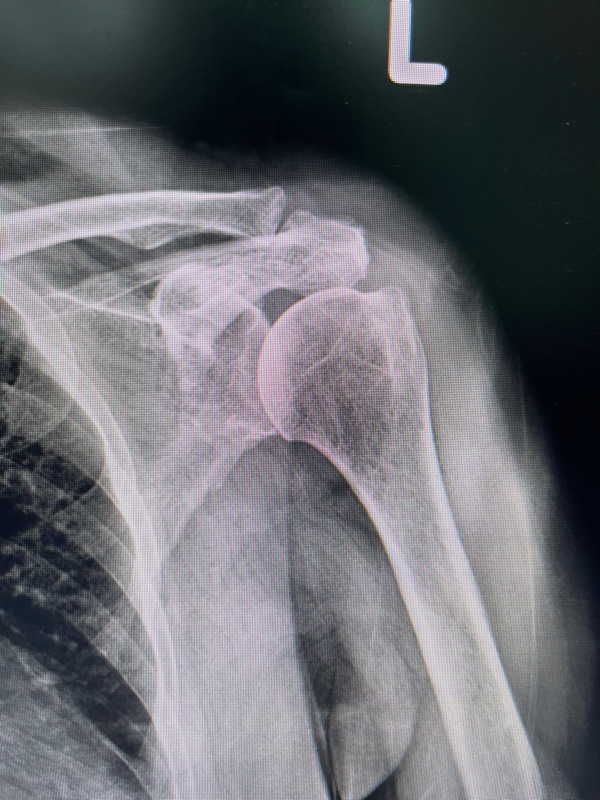

3. การบาดเจ็บจากอุบัติเหตุ

อุบัติเหตุ เช่น การลื่นล้ม หรือการออกแรงผิดท่า อาจทำให้กล้ามเนื้อไหล่ฉีกขาด หรือข้อไหล่หลุดได้ ซึ่งจะทำให้ปวดแบบเฉียบพลันและรุนแรง

รีบพบแพทย์ทันทีเพื่อทำการตรวจและรักษา